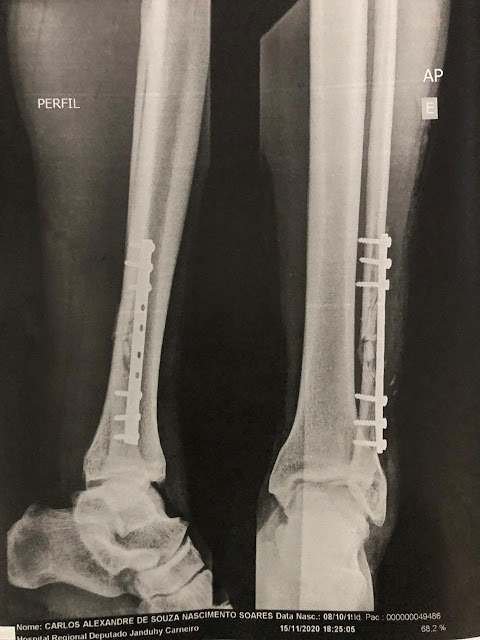

Pós cirurgia.